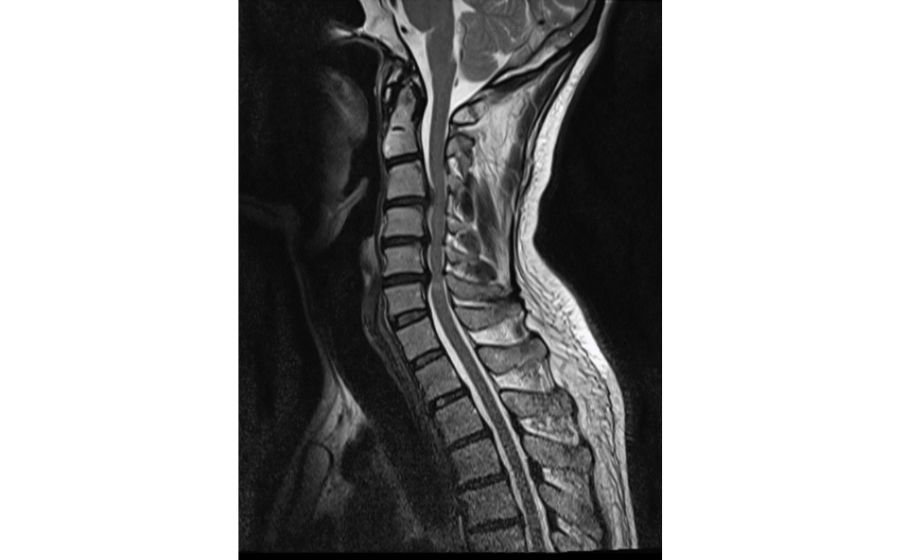

Cervical Myelopathy

Cervical myelopathy occurs when the spinal cord in the neck is compressed due to disc degeneration, ligament thickening, or arthritis. This pressure can cause imbalance, hand clumsiness, difficulty walking, and weakness in the arms or legs. Early diagnosis with MRI is crucial because symptoms can gradually worsen over time. Treatment focuses on decompressing the spinal cord—often through ACDF, cervical disc replacement, or posterior decompression—to prevent progression and improve function. Surgery aims to protect the spinal cord, restore stability, and enhance mobility and quality of life.